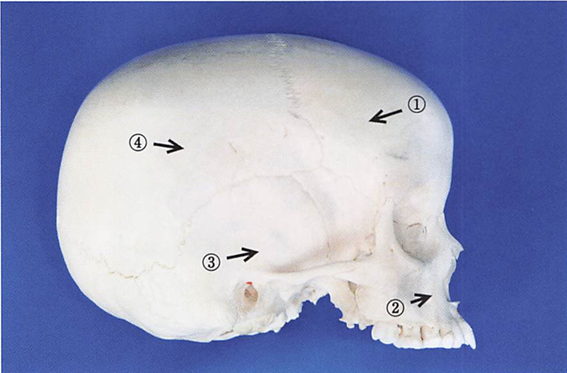

午前-53

頭蓋骨の写真を別に示す。 Scammon〈スキャモン〉の臓器発育曲線で一般型の成長を示すのはどれか。1つ選べ。

a. ①

b. ②

c. ③

d. ④

解答を見る

b